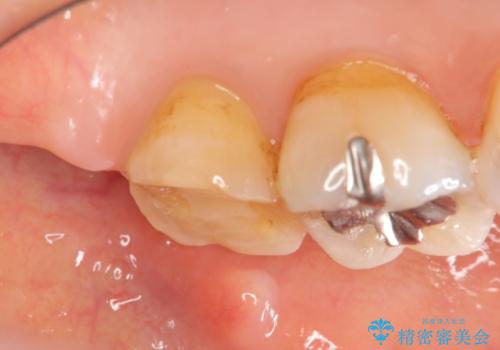

- 根管治療ののち、そのままになっていた歯のクラウン製作を希望され来院されました。

クラウンの将来的な虫歯の再発を防ぐために周囲の歯ぐきを切除することで歯の高さを出し安定した歯周環境にしたのち噛み心地の良いゴールドクラウンを製作します。

クラウンを装着した歯の虫歯の再発を防ぎ長い予後を期待するために削った箇所をしっかりとかぶせる適合の良さが必要はもちろんですが、セメントの漏洩を防ぐためにクラウンの十分な支台高径を歯周外科を行い獲得しました。